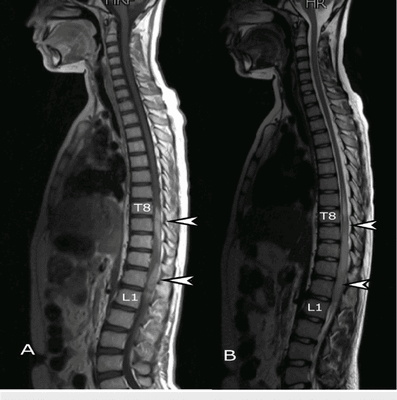

По статистике одна из самых частых находок на МРТ позвоночника у людей старше 35 лет - это межпозвоночная грыжа или протрузия в зоне шейного отдела позвоночника или пояснице. Грыжи грудных межпозвонковых дисков как осложнение грудного остеохондроза, встречаются с частотой 1 случай на 500-700 тысяч населения. Магнитно-резонансная томография, несомненно, считается одной из самых показательных диагностических методик в визуализации патологий межпозвоночных дисков. Здесь врач получает возможность обнаружить на снимках прямые признаки присутствия межпозвоночных грыж, их величину, а также позвоночные протрузии - предгрыжи. Другим томографическим исследованием позвоночника является компьютерная томография. На снимках, полученных при КТ-диагностическом исследовании, врачи тоже смогут распознать грыжи. А какое из этих двух исследований наиболее показательное, разберем подробно ниже.

Эффективность применения КТ и МРТ в диагностике межпозвоночных грыж зависит от срока заболевания и сагиттального размера грыжевого выпадения. МРТ более информативна при длительности заболевания менее 1 года и при небольших размерах грыжевого образования. При КТ высока достоверность обнаружения грыжи только с длительным сроком существования и большими размерами. При сравнении с КТ и МРТ, более эффективна в диагностике грыж магнитно-резонансная томография. КТ диагностика уступает МРТ в способности визуализировать грыжи. Поскольку компьютерная томография - это рентгенологическое обследование, то на снимках лучше всего отображаются костные структуры позвоночника, и косвенными признаками грыжи будут костные деформации позвонков. К сожалению, сканирование позвоночника на наличие протрузий с помощью КТ в редких случаях позволяет с точностью найти и определить проблему.